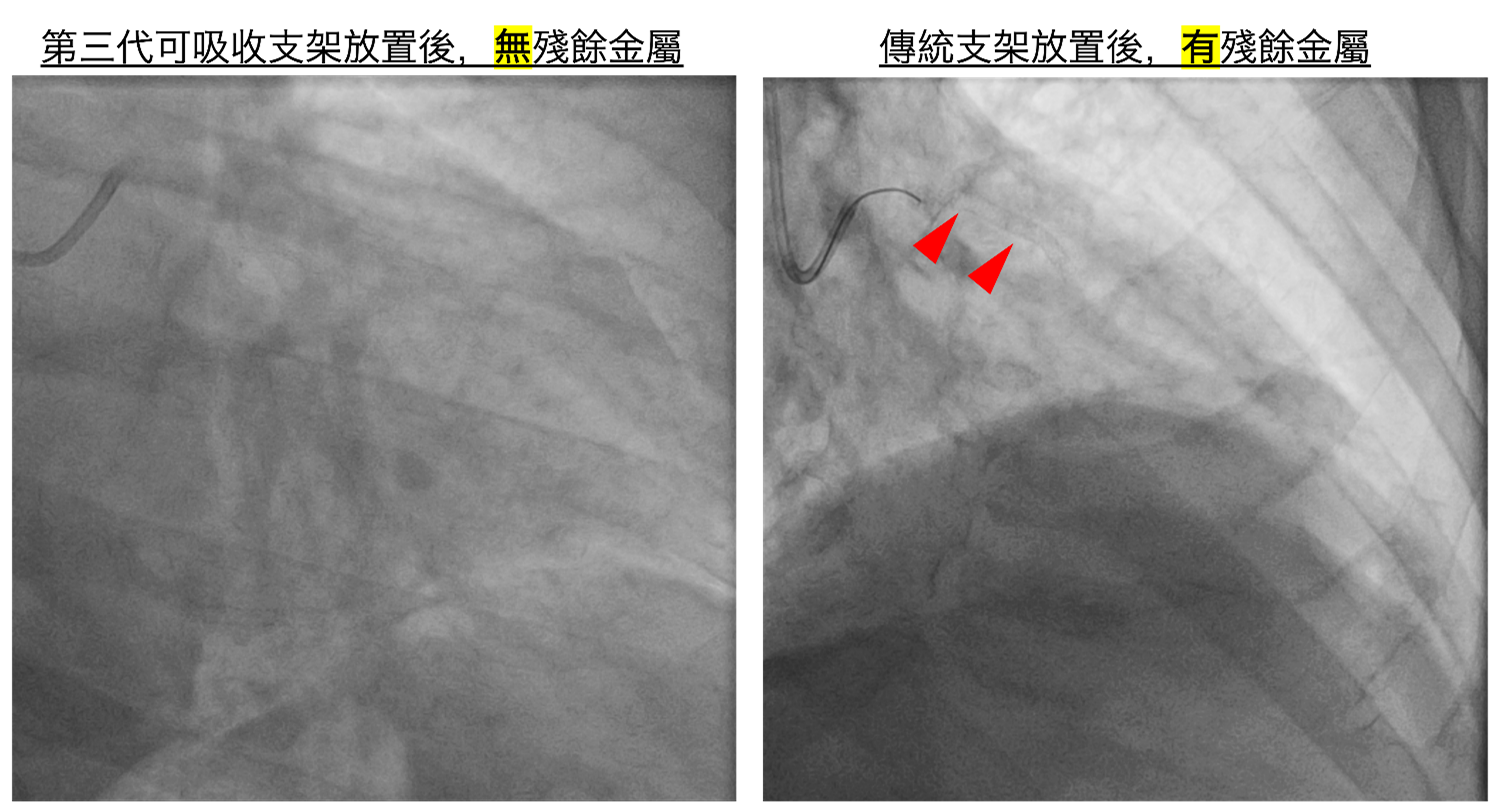

圖二、放置第三代可吸收支架,一年內約99%會被身體吸收,不會殘留異物或造成長期發炎。(非患者本人)

年輕患者若以傳統金屬支架治療,血管會因永久性金屬結構而失去自然舒縮能力。第三代鎂合金可吸收支架初期能穩定撐開血管,一年內約99%會被身體吸收,不會殘留異物或造成長期發炎,對保留未來血管健康十分有利。但前提須血管無嚴重鈣化、長度短、無大分支之情形,才能評估使用。